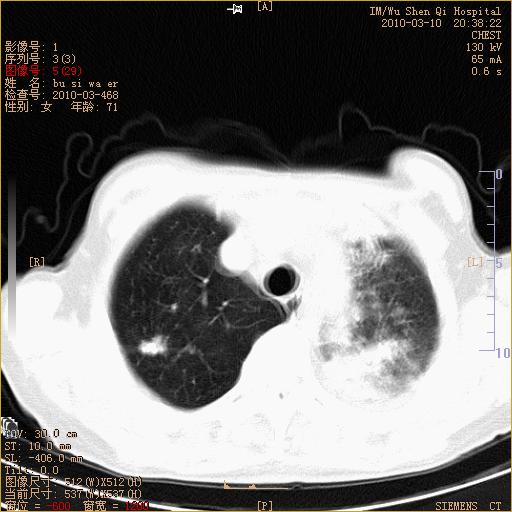

以下是引用随光逐影在2010-3-11 0:41:00的发言:[br]1)考虑左肺及右肺上叶继发性肺结核并左肺炎症感染。2)左侧支气管内膜结核可能;建议必要时行纤支镜检查。3)肺气肿。4)心包膜增厚(或少量心包积液)。5)左侧胸腔积液。